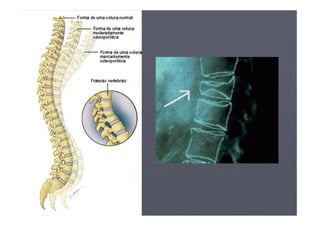

► A osteoporose progride sem sintomas ou dor, até

que ocorra alguma fratura. As partes mais

vulneráveis às fraturas são: bacia, colo do fêmur,

coluna e punho.

OSTEOPOROSE

►2,4 milhões de fraturas decorrentes da

osteoporose ocorrem anualmente no Brasil;

►50% delas são na coluna vertebral e 25%

► Isto acontece quando as vértebras da coluna se

achatam com um simples tossir ou quando se

levanta qualquer peso, por mais leve que seja.

DENSITOMETRIA ÓSSEA

►Este achatamento ou colapso das vértebras

é extremamente doloroso.